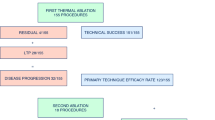

From September 2015 to September 2017, 69 MWAs were performed in 54 patients, achieving technical success in all cases and treatment completion without deviations from the standardized protocol in 61 procedures (88.4%). Immediate post-MWA CT scans showed ablation dimensions smaller by about 25% than in the ex vivo model; however, a remarkable volumetric increase (40%) of the treated area was observed at 1 month post-ablation. No treatment-related deaths nor complications were recorded. Treatments of equal power and duration yielded fairly reproducible ablation dimensions at 48-h post-MWA scans. In comparison with the ex vivo liver model, in vivo ablation sizes were systematically smaller, by about 25%. Overall LPR was 24.7%, with an average TLP of 8.1 months. OS rates at 12 and 24 months were 98.0% and 71.3%, respectively.

The main features of patients and tumors are reported in Table 2. Technical success (i.e., complete tumor ablation, with margin) was achieved in all cases (69/69). However, the planned treatment protocol, based on the use of a single antenna without probe re-positioning nor power variations, was performed in 61 out of the overall 69 treatments (88.4%). In the other 8 treatments (11.6%), two consecutive overlapping ablations were performed for ensuring complete tumor coverage with safety margins, due to the impossibility of precisely accessing the target tumor along its longest axis. These 8 treatments were excluded from the evaluation of MWA repeatability and comparability with the ex vivo bovine liver model and retained only for safety and efficacy assessments.

LPR and DPR of 24.7% and 33.3% were reported (TLP: 8.1 ± 6.0 months; TDP: 9.0 ± 7.0 months); a remarkably higher DPR was registered in MALT2 (54.3% vs 4%). Subgroups analysis for LPR is shown in Table 4.

Over the entire MALT cohort, estimated OS and LPFS rates at 12 and 24 months were 98.0% and 71.3%, and 80.2% and 64.7%, respectively (Fig. 5). MALT1 resulted in OS = 95.7% and LPFS = 71.4% at 12 months, and OS = 78.1% and LPFS = 62.5% at 24 months; MALT2 yielded OS = 100.0% and LPFS = 68.6% at 12 months, and OS = 81.6% and LPFS = 64.6% at 24 months. No statistically significant difference was demonstrated between the two arms (p = 0.456 for OS and 0.461 for LPFS).